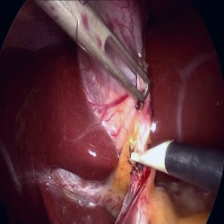

Refer to caption

Figure 2: The generalization of the pretrained encoder was evaluated across various downstream tasks, such as (a) workflow classification, (b) action classification, (c) segmentation, and (d) diagnosis